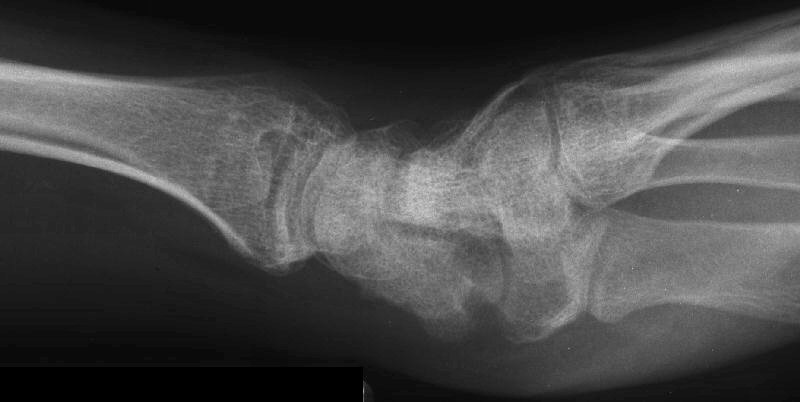

Healed.

The patient requested hardware removal prior to enlisting for military duty. Final films.